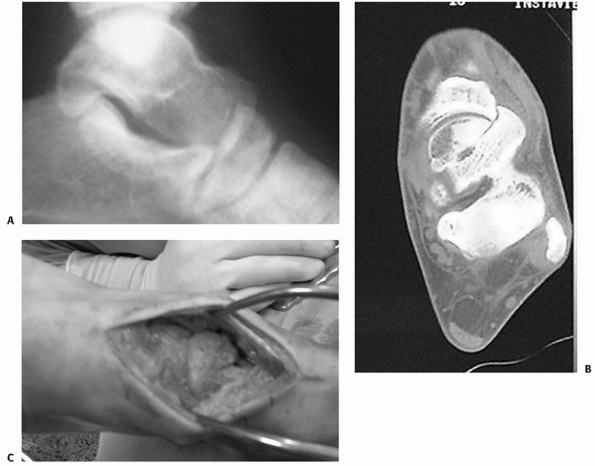

variety of plain radiographic views are important to visualize the

comminution and alignment. Canale and Kelly19,20

described a view of the talar neck achieved by internal rotation of the

foot by placing the foot plantigrade on an x-ray film and angling the

beam at 75 degrees to the perpendicular. Pronation of the foot or

internal rotation of the limb will achieve rotation of the talus such

that the medial aspect of the talar neck can be well visualized. This

view is particularly useful intraoperatively to assess the

reconstruction of a talar neck fracture with associated medial

comminution and to confirm that varus malalignment has been avoided (Fig. 58-1).

calcaneus, as associated fractures of the posterior facet can often be

seen. A true lateral view of the subtalar joint can be beneficial to

assess for comminution and subluxation (Fig. 58-2). Oblique views of the talus are helpful in diagnosing posterior process fractures.46

FIGURE 58-1 Canale and Kelly view of the foot. The correct position of the foot for x-ray evaluation of the talus is shown.